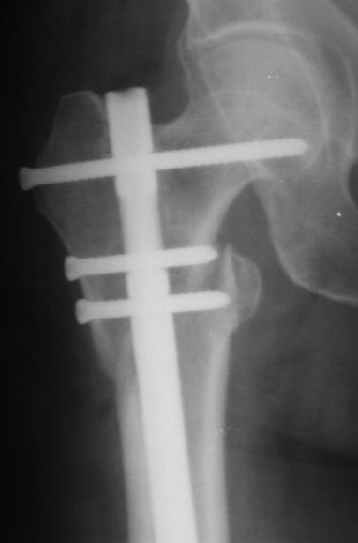

Это было года 2,5 назад, мы тогда еще уточняли возможности шинирования с угловой стабильностью гвоздем с поперечным расположением винтов при переломах проксимального отдела бедра. Пациенту не пришлось приобретать намного более дорогой рекон или проксимальный гвоздь. В приложении еще несколько примеров применения того гвоздя при высоких переломах бедра, в том числе с более латеральной точкой входа. Гвоздь изгибаем для этого.